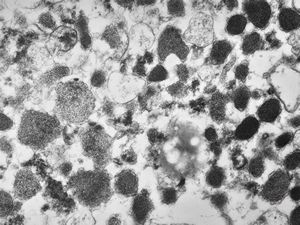

M, 38y. | pheochromocytoma